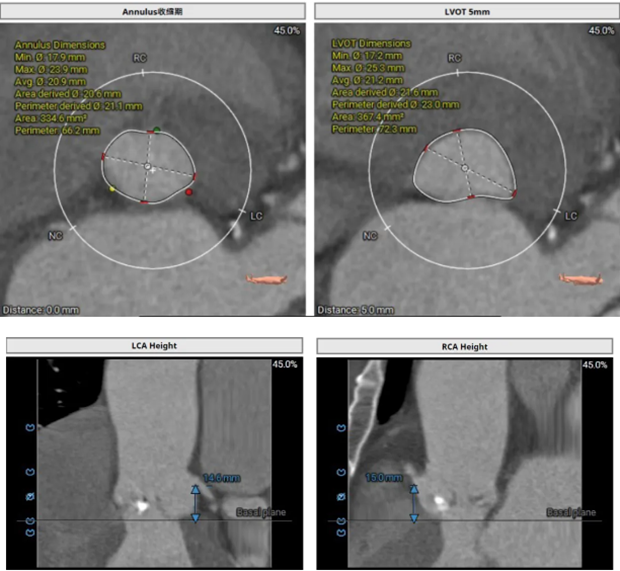

▲ 术前建模测量

TAVR手术的成功离不开先进的医疗技术和设备支持,以及医护团队的协作。团队利用高精度影像设备进行术前评估,术中实时监控,确保导管和人工瓣膜的准确定位,并采用最新一代的人工瓣膜材料,具有更好的生物相容性和耐久性,减少术后并发症。TAVR的微创特点大大缩短了患者的术后恢复时间。